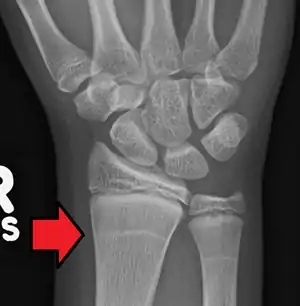

Growth arrest lines, also known as Harris lines, are lines of increased bone density that represent the position of the growth plate at the time of insult to the organism and formed on long bones due to growth arrest. They are only visible by radiograph or in cross-section. The age at which the lines were formed can be estimated from a radiograph. Harris lines are often discussed as a result of juvenile malnutrition, disease or trauma. Other studies suggest a reconsideration of Harris lines as more of a result of normal growth and growth spurts, rather than a pure outcome of nutritional or pathologic stress.[1] The term is named after Henry Albert Harris, 1886-1968, professor for anatomy at the University of Cambridge.

| Growth arrest lines in a child with an underlying bone disease | |